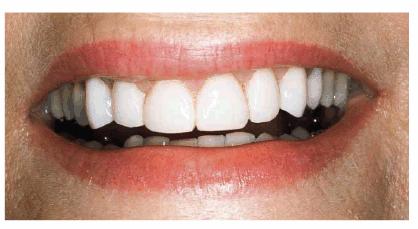

Figure 24-2A: This patient was dissatisfied with her crowded anterior teeth. Note how the gingival height differs between the central and lateral incisors.

Figure 24-2B: The dissimilar gingival heights did not bother the patient because her natural smile line concealed these irregularities.

Figure

24-2C: After a slight reproportioning of the six anterior teeth, direct

composite resin was placed and contoured (6-mm ET [Brasseler,

Figure 24-2D: The final result shows improved proportion in tooth size and form.